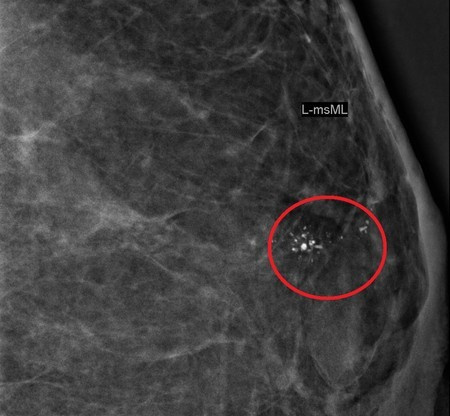

要分辨钙化点为良性或恶性,医生会观察钙化点的形状和分布来判定。良性钙化点在影像学上的特色是均匀分布、有对称性,通常两边乳腺都有;形状也较为规律,例如圆形、爆米花状、茶杯状等等。

钙化点3种情况 有恶性疑虑

如果医生判定为良性钙化点,定期复查即可。但如果钙化点有以下3种情况,就要小心可能是恶性钙化点:

1. 钙化点成簇聚集,集中在局部乳腺。

2. 不规则外形,例如分岔状、线形、 棒状、多角形等。

3. 钙化点周边乳房组织密度有变化。